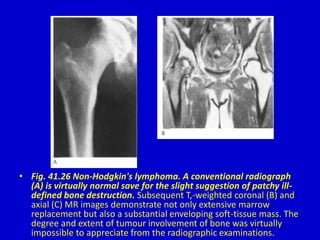

• Fig. 41.26 Non-Hodgkin's lymphoma. A conventional radiograph

(A) is virtually normal save for the slight suggestion of patchy ill-

defined bone destruction. Subsequent T,-weighted coronal (B) and

axial (C) MR images demonstrate not only extensive marrow

replacement but also a substantial enveloping soft-tissue mass. The

degree and extent of tumour involvement of bone was virtually

impossible to appreciate from the radiographic examinations.